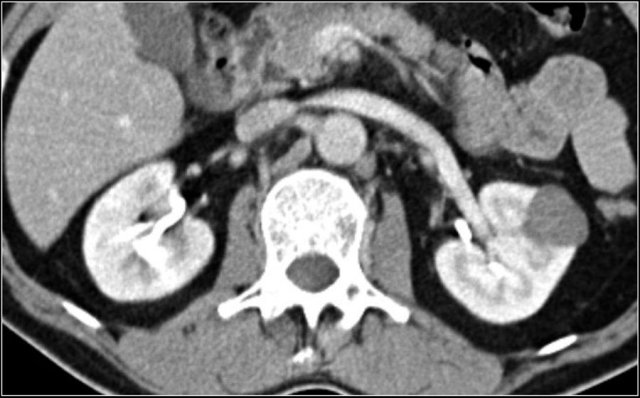

In this case there are hypodense areas in both kidneys.

Based on the imaging alone the main differential is multifocal pyelonephritis, lymphoma and metastases.

This patient had a urinary tract infection and episodes of flank pain and there was no history of a primary tumor or lymphoma.

So the diagnosis is pyelonephritis.

A CT scan 4 months later shows normal enhancement of both kidneys; the renal abnormalities on the first scan were therefore consistent with an episode of multifocal pyelonephritis.